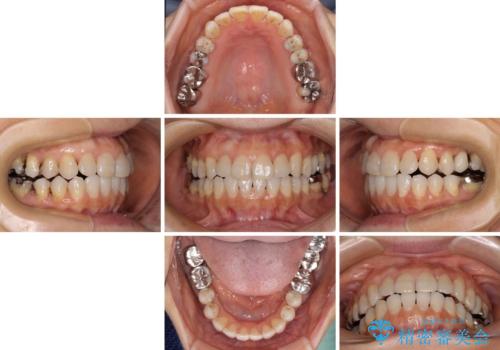

前歯の突出感と上下の隙間 インビザラインによる矯正治療

- 前歯の上下スペースと前歯の隙間を気にして来院された患者様です。

インビザラインにより上下の前歯の隙間を閉じながら、IPRを用いて口元の突出感を合わせて改善していくこととしました。

上下の隙間に舌が入り込むことが、すきっ歯やオープンバイトの原因であったため、舌の筋肉のトレーニングも並行して行い、後戻りの抑制を図りました。